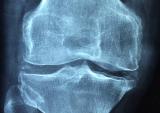

Артрозы, и в общем, и, в частности, заболевания тазобедренных и коленных суставов (коксартроз, гонатроз), распространены в Армении и встречаются приблизительно с одинаковой частотой...